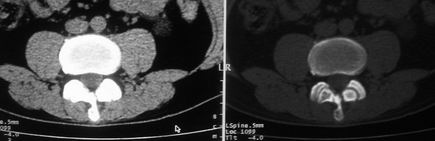

以下是引用余辉在2008-10-23 16:14:00的发言:[br]腰椎体棱角分明,小关节退变部分隔合,骶髂关节部分融合,考强脊炎